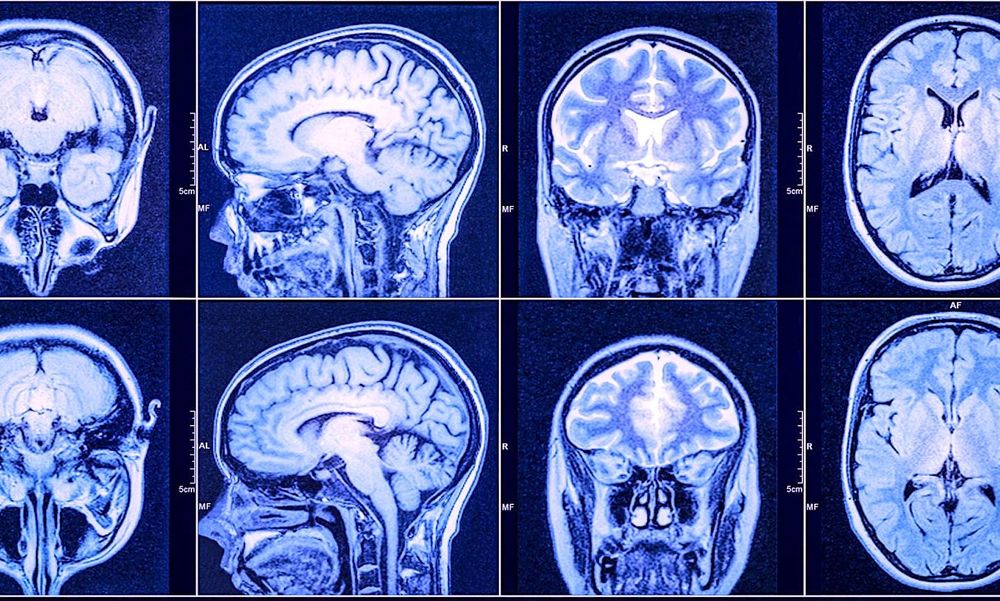

Le glioblastome est la tumeur cérébrale la plus agressive et fréquente, son taux de survie étant encore aujourd'hui très faible (5% à 5 ans). Récemment, des chercheurs de l'Institut de recherche sur le cancer (ICR) et de l'hôpital Royal Marsden de Londres ont accompli une avancée très encourageante en testant un traitement innovant, qui a permis de faire disparaître une tumeur avancée chez l'un des sujets de l'étude.

Suite au traitement, Hamish Mykura, 59 ans, a vu sa tumeur disparaître des scanners. On lui a diagnostiqué un glioblastome en août 2018, et il a été orienté vers le Royal Marsden pour un traitement qui comprenait une chimiothérapie et une radiothérapie, en plus d'une chirurgie à l'hôpital St George. Lorsque le traitement a cessé de fonctionner et que le cancer a commencé à se développer en août 2019, il a rejoint l'essai Ice-Cap. Vingt mois plus tard, Hamish n'a plus de cancer visible.